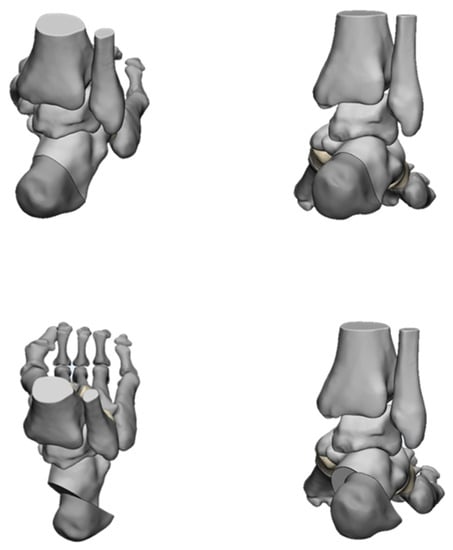

4.2. Radiological Evaluation